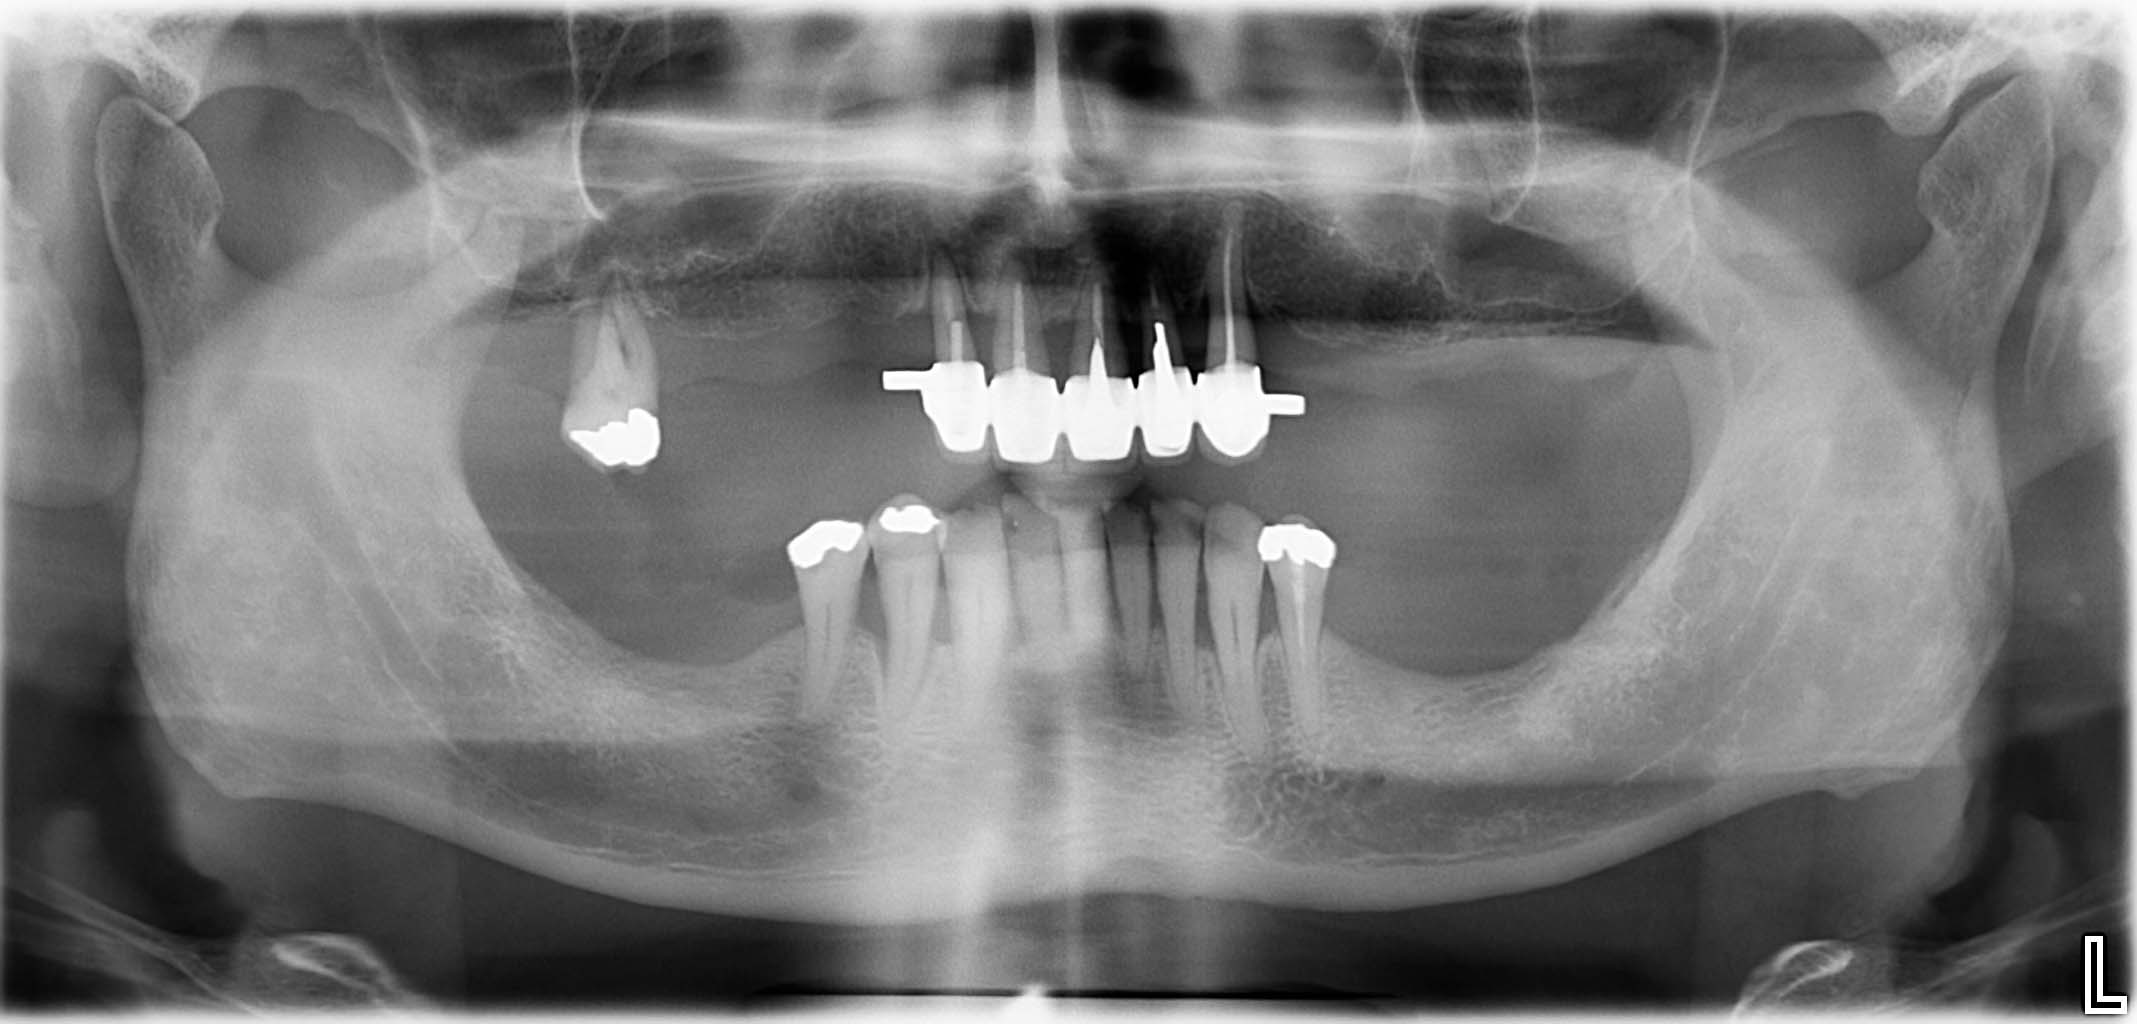

Erfolgreich implantierte Patientenfälle (klinische Fotos)